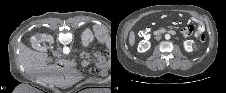

Immediate post-ablation CT scan and follow up

The final CT scan is performed immediately after ablation with IV contrast (50% of standard dose) to confirm successful ablation. A rim of demarcation seen around the ablation zone signifies a successful treatment. The immediate post-ablation scan is also important to identify complications such as bleeding. Figure 4a represents the tissue changes expected to be seen immediately after ablation.

The American Urological Association guidelines10 recommend obtaining cross sectional imaging with either CT or MRI 3-6 months after ablation and this serves as a baseline to compare future scans. Thereafter, annual abdominal scans are recommended for 5 years. Figure 4b shows the typical "halo" scar expected to be seen several months after ablation. Absence of enhancement on CT or MRI has been shown histologically to be consistent with cancer kill.12 Thus, the urologist should be suspicious of treatment failure or local recurrence when imaging reveals a visually enlarging neoplasm or new nodularity in the ablation zone that enhances with contrast.

Figure 3. A) A bilobed shaped 4 cm right sided tumor is shown. The probe was initially deployed on the inferior aspect of the tumor with tines seen extending into a rim of normal parenchyma. The first ablation was then performed. B) After completion of the first ablation, the probe was repositioned to address the superior aspect of the tumor. After proper probe placement, the second ablation cycle commenced.

Figure 4. A) Immediate post-ablation scan with IV contrast showing a rim of demarcation around the ablation zone. This represents a successful treatment. B) The typical "halo" scar expected to be seen several months after ablation. This particular example is of a left renal mass 12 months after RFA.